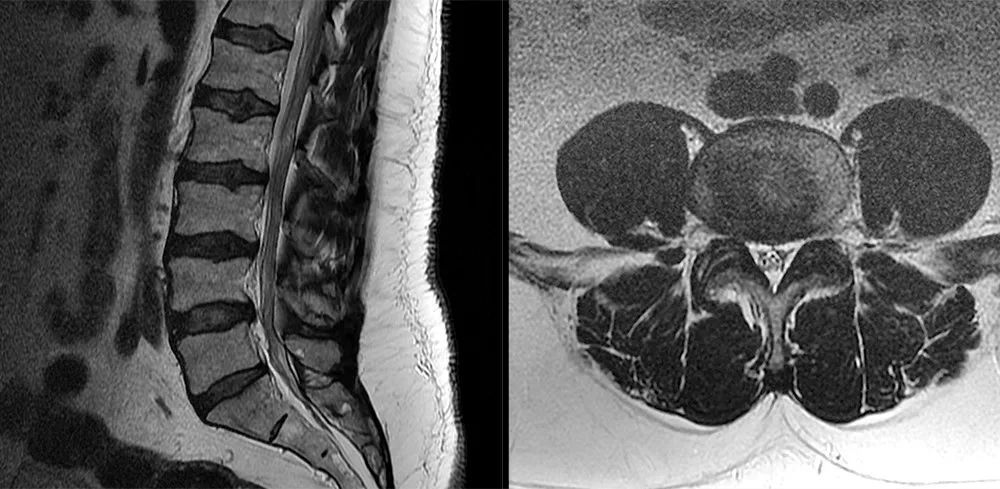

• 椎管内硬膜外脂肪增多症与终丝脂肪沉积

• 常见易忽略的疾病—椎管内硬膜外脂肪增多症

• 椎管内硬膜外脂肪增多症